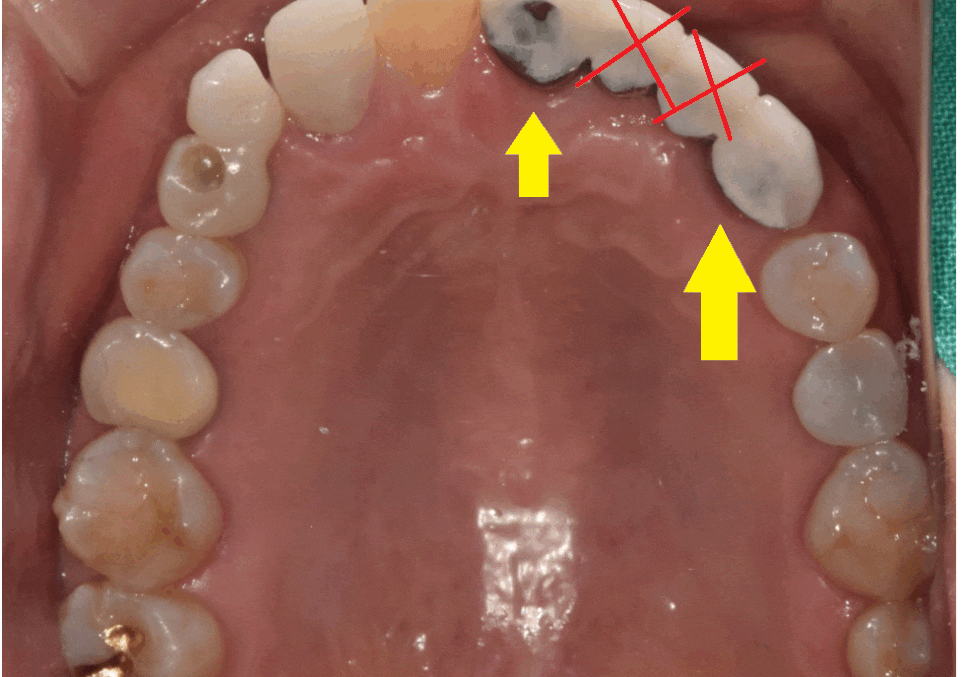

그리고 치아가 상실된지 오래되어

치아가 쓰러져 자리가 부족할 때

임플란트 수술 대안으로 브릿지를 합니다.

위에 환자분도 치아가 빠진지 워낙 오래되어

저 좁은 공간에 치아 3개가 들어가야했습니다.

240408

임플란트는 뼈에 심는건데

공간이 안나오면 브릿지로 대체하죠~